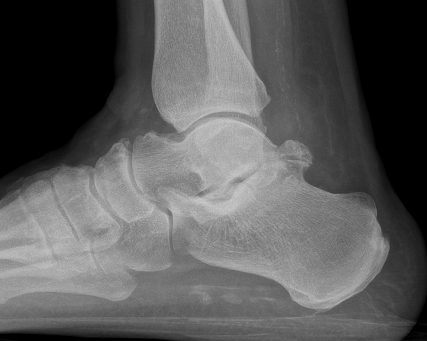

CT

Subluxation of TNJ with advanced STJ OA

TNJ OA with posterior / medial / anterior facet OA of the subtalar joint